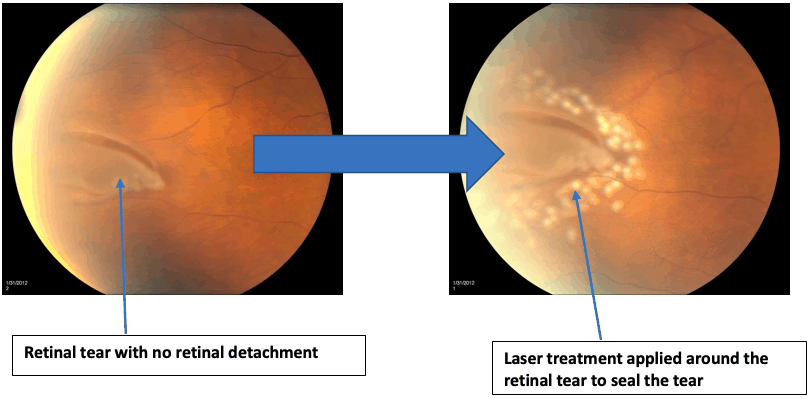

What is the treatment for Retinal Tears?

In the case above, we have a retinal tear with no retinal detachment. The treatment in this case would be to perform laser retinopexy which is a clinic-based laser.

In a laser retinopexy, laser is applied all around the tear. This helps to seal the tear and prevent vitreous from entering through the tear and detaching the retina.

This clinic-based laser can only be performed if there Is no retinal detachment. If there is retinal detachment, surgery will be needed. So it is important to find and treat retinal tears early before they become retinal detachments.